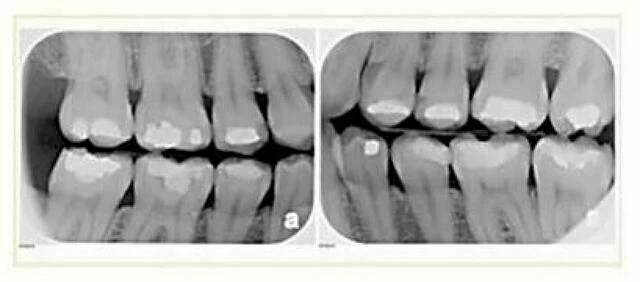

c. Phim cánh cắn: Xác định sâu răng và mức xương tại những răng cần trước khi bắt đầu điều trị chỉnh nha trong 2 năm.